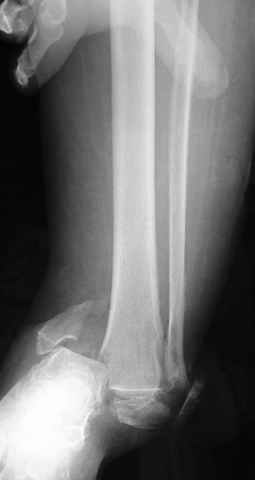

Dear all,40 y.o. man had sustained this terrible fracture falling from a motorbike.

Closed fracture.

This is really Pilon Fx (C3.3; the high energy and the extent of distal tibia comminution are defining it).

I would put simple unilateral, medially positioned external fixator (two pins in calcaneus - not to violate talus needed for later fusion, two in tibia), allow soft tissues to recover and in 2-3 weeks I would do delayed ankle fusion.